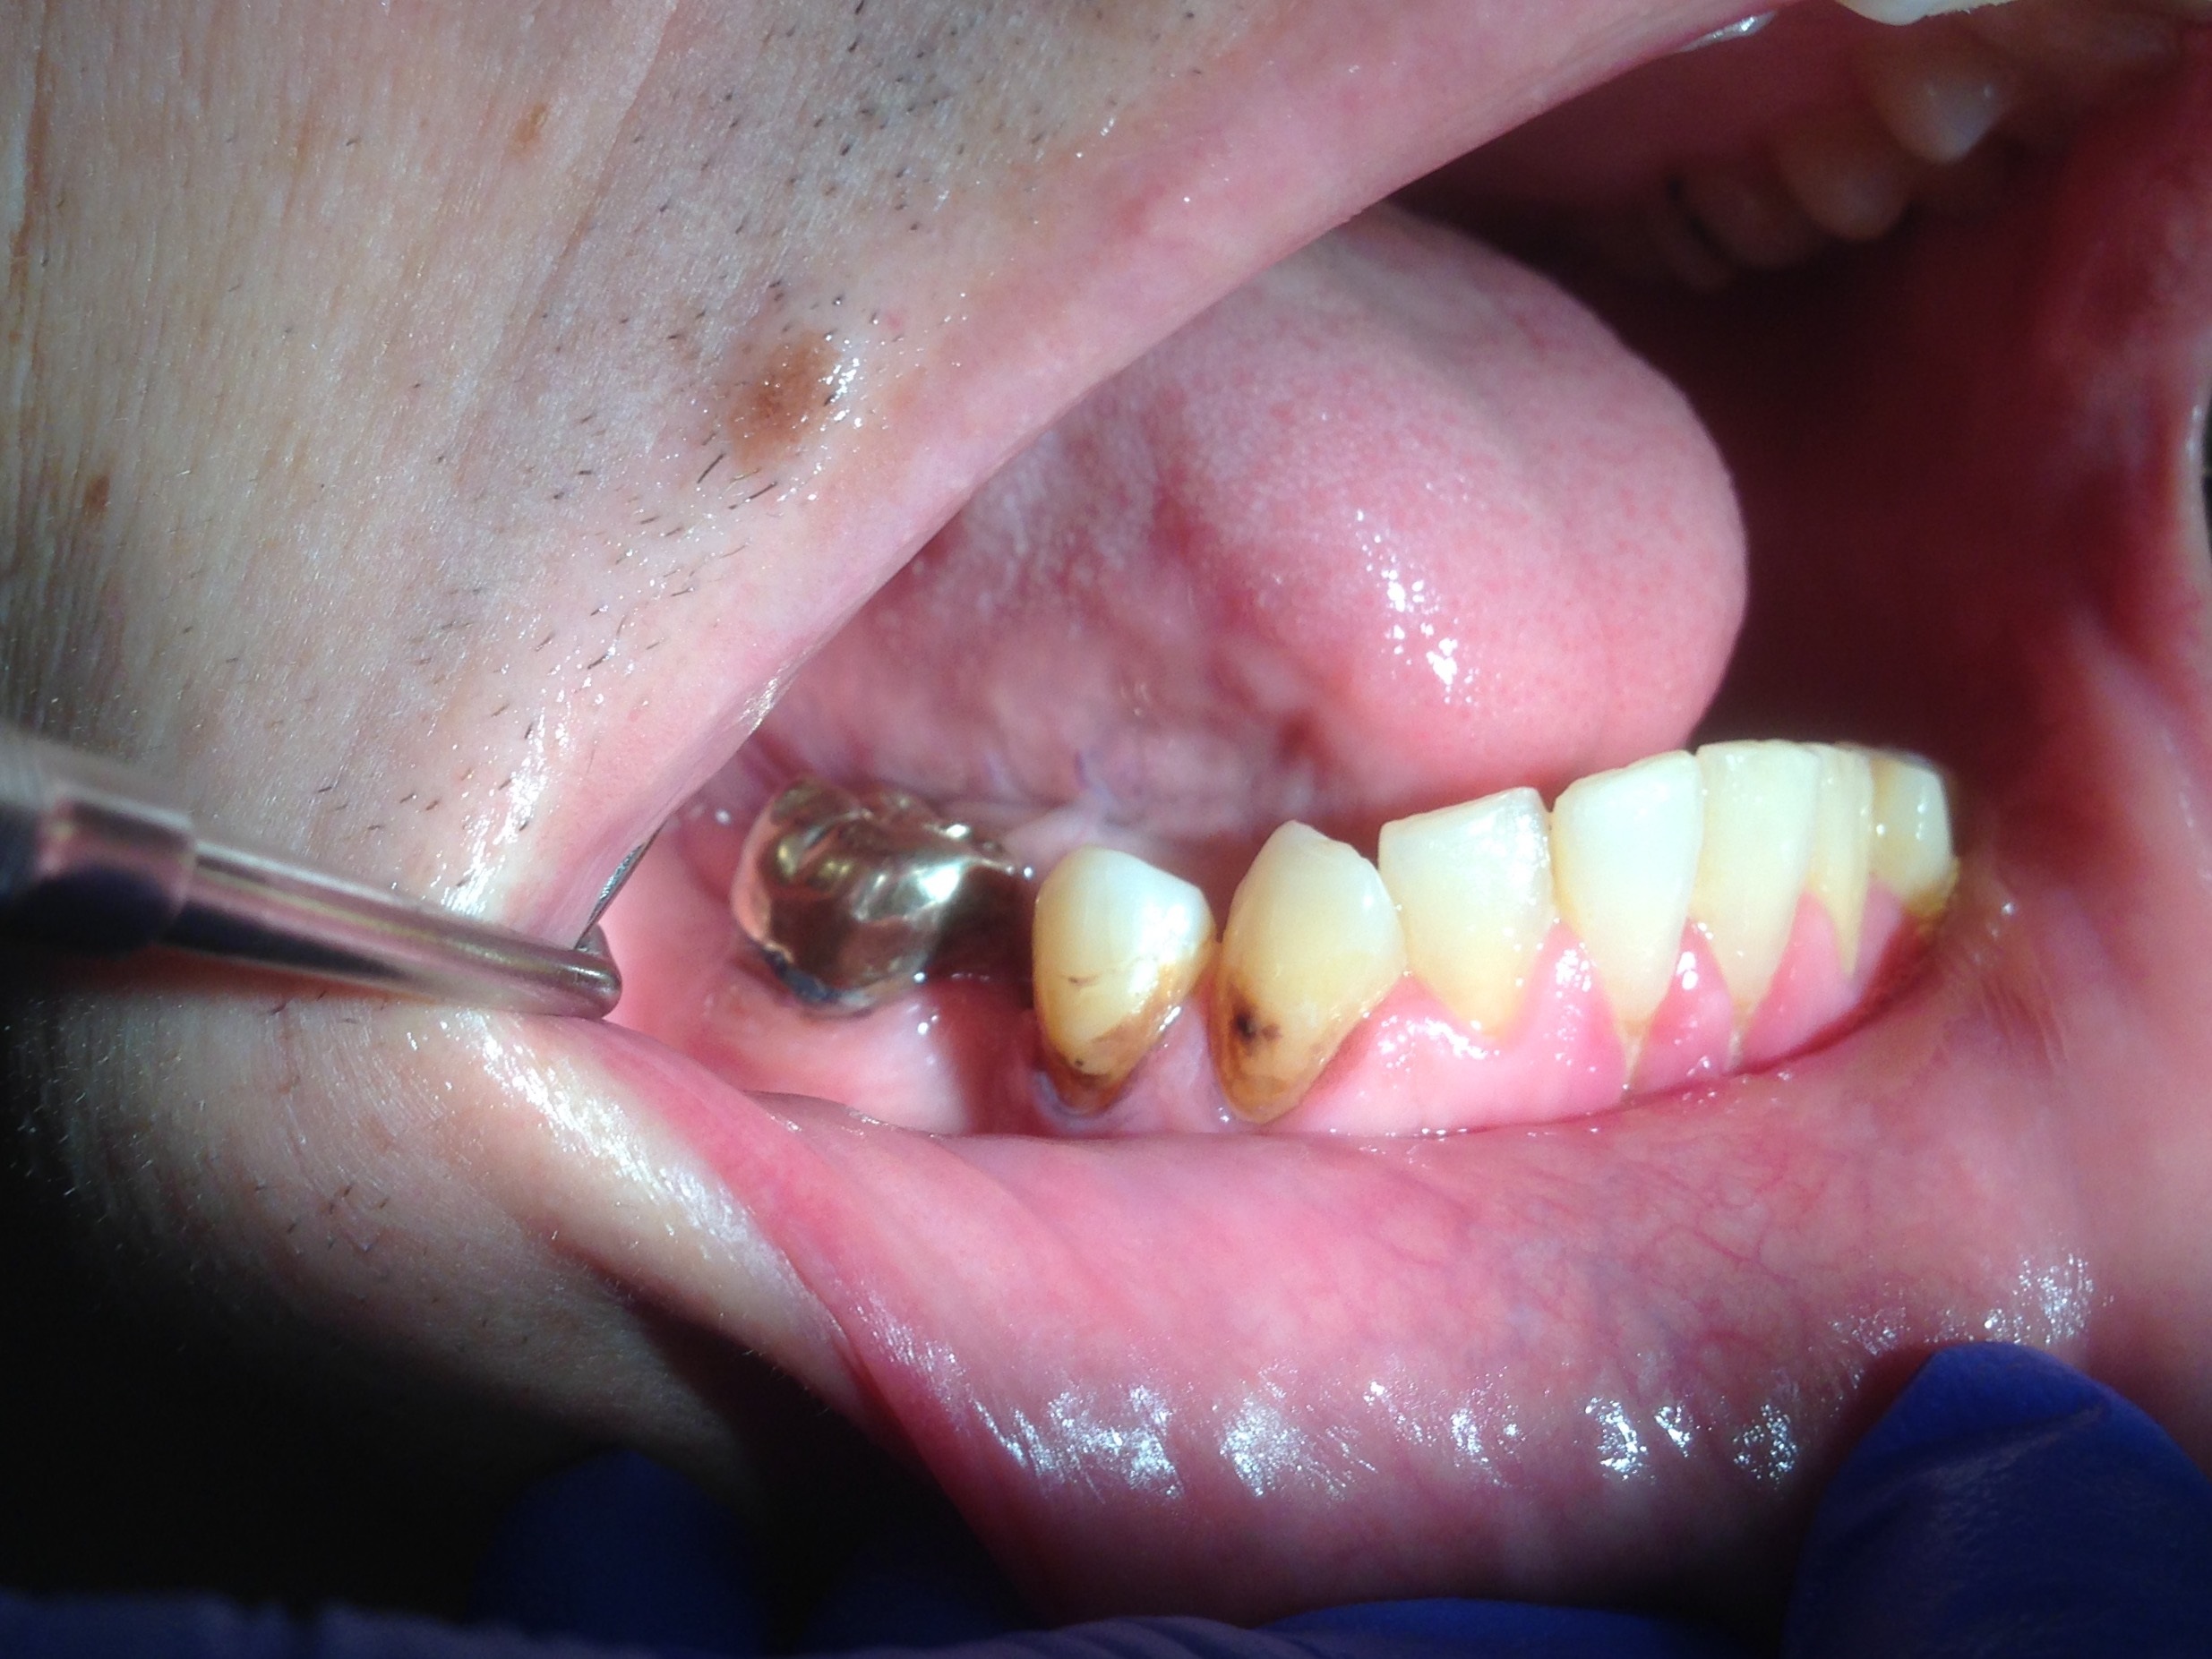

The patient shown in Figure 4 through Figure 6 was a meth user for 6 years. He had a stroke at age 22. After recovering from the stroke and stabilization of his circulatory system was achieved, and once he quit using meth, he strongly desired to apply for a job and wished to improve his dental appearance. He opted to have all of his teeth extracted, as complete dentures were his only treatment option because there were no adequate abutment teeth remaining for placement of removable partial dentures.

Fig 4 through Fig 6. Patient’s oral condition after 6 years of meth use.